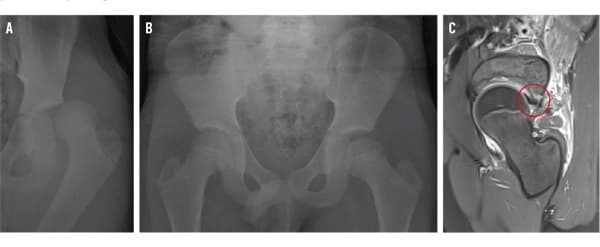

Venstresidig hofteluksation

Sikker kirurgisk hoftedislokation til behandling af skader efter traumatisk hofteluksation hos børn